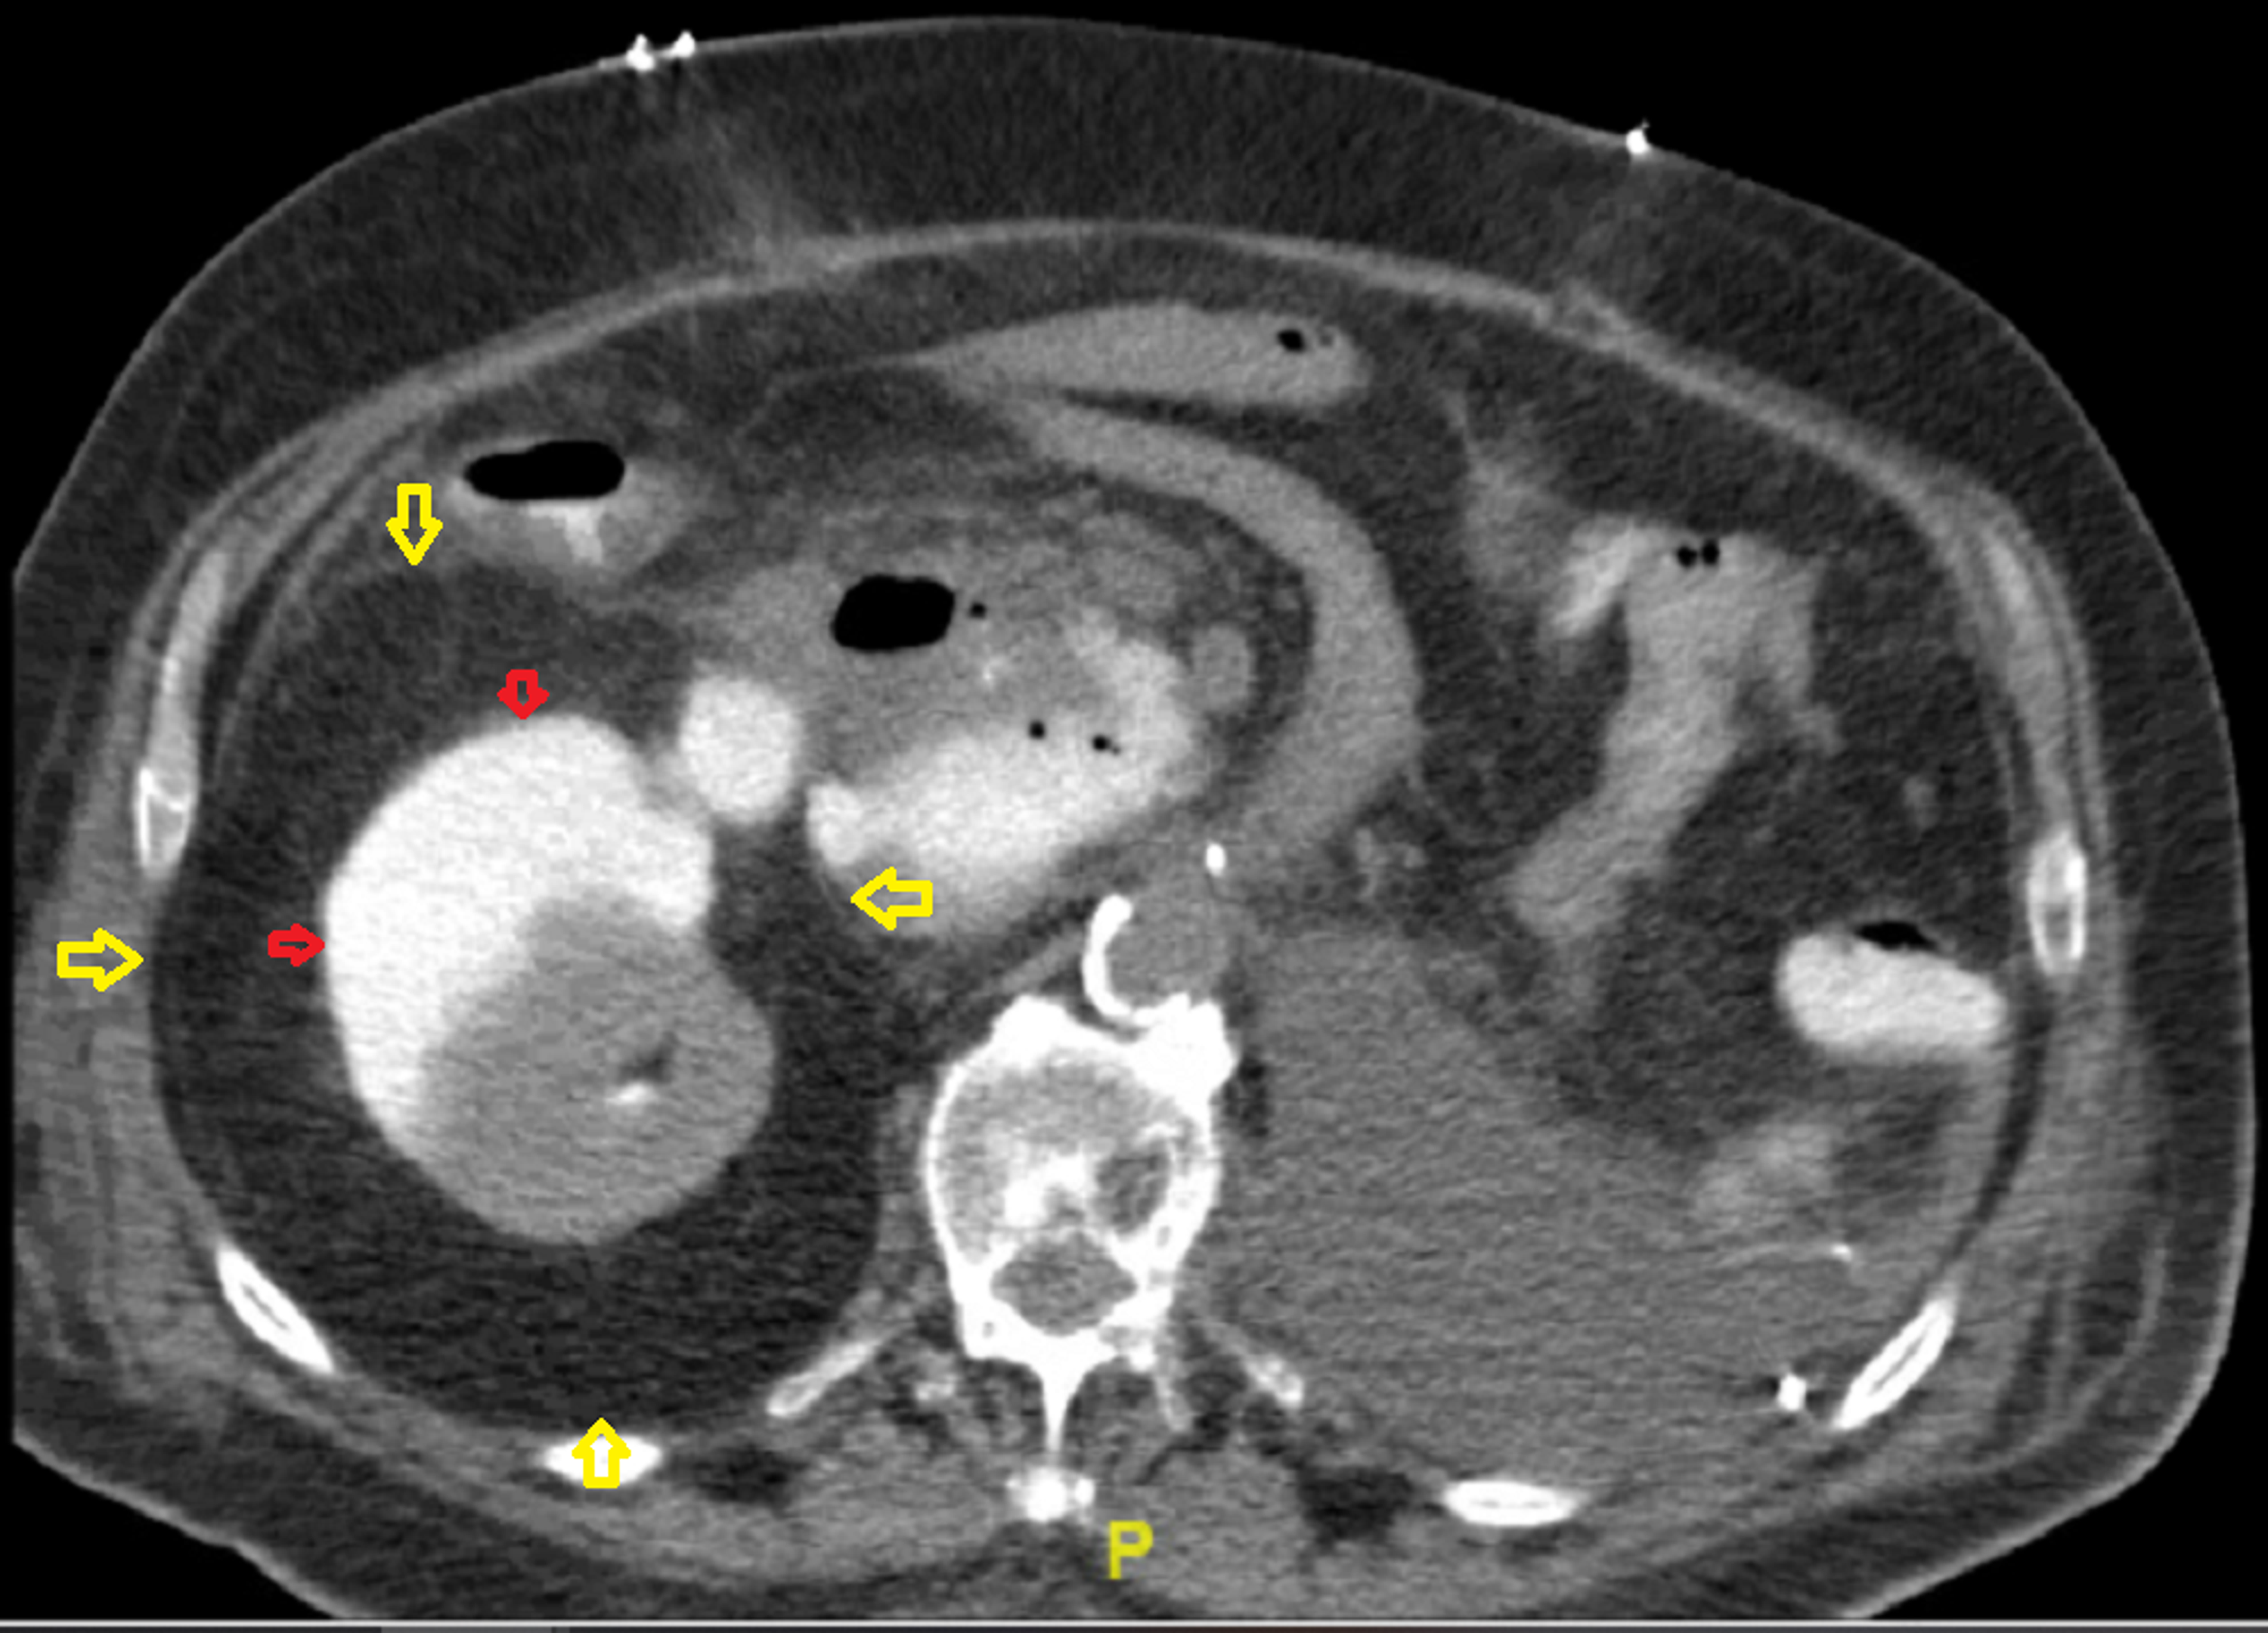

(PDF) Perirenal Transplant Fluid Collections Post Renal Transplant Fluid Collections We were evaluating a kidney transplant recipient three weeks after surgery who presented with a rise in. Delay in recognizing and management can lead to graft. Perirenal transplant fluid collections can be associated with renal transplants at any time in the immediate postoperative period to many months. Perirenal fluid collections are a common surgical complication postrenal transplant that may lead. Post Renal Transplant Fluid Collections.